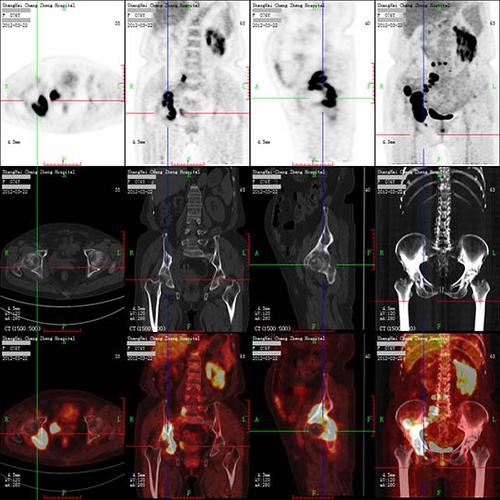

霍奇金**细胞淋巴瘤治疗前全身petct